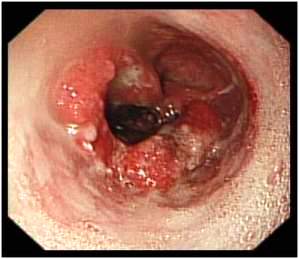

Bronhoskopija -je metoda kojom se potvrđuje dijagnoza.

Izvodi se u lokalnoj ili opštoj anesteziji uvođenjem endoskopskog tubusa

kroz nos ili usta i uzimanjem uzorka sa sumnjivog mesta - biopsija tumora

koji je neophodno patohistološki verifikovati.